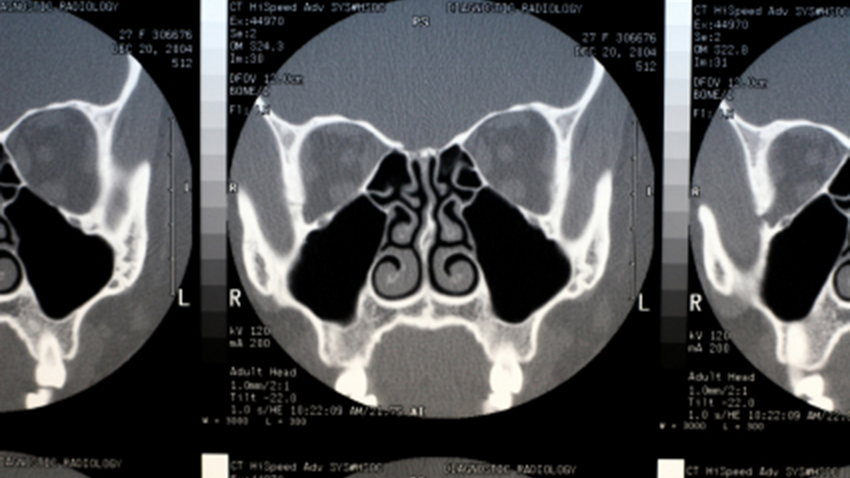

Acute sinusitis causes the spaces inside your nose (sinuses) to become inflamed and swollen. this interferes with drainage and causes mucus to build up. with acute sinusitis, it might be difficult to breathe through your nose. the area around your eyes and face might feel swollen, and you might have throbbing facial pain or a headache. acute sinusitis is mostly caused by the common cold. unless a bacterial infection develops, most cases resolve within a week to 10 days and home remedies may be Penanganan sebaran konten hoaks vaksin covid-19 jumat (30/04/2021) virus corona varian baru b. 117, b. 1351, b. 1617 sudah terdapat pada indonesia. What is the z-pak used to treat? the z-pak is a 5-day course of azithromycin (zithromax), an antibiotic. it’s used to treat certain bacterial infections, including some sinus infections and upper respiratory tract infections that lead to:. Lokalguiden visar här en ledig lokal för kontor på isafjordsgatan 30b, kista, kista. lokalen har objektsnummer 41945802 och förmedlare är kungsleden .

12 feb 2020 kista ovarium adalah gangguan yg identik terjadi dalam perempuan . ternyata, kista ovarium juga dapat terjadi dalam remaja. baca selengkapnya . See full list on cdc. gov. Sinusitis (or rhinosinusitis) is inflammation in the nasal cavity and the paranasal sinuses, which may be acute, recurrent acute, subacute or chronic. acute . Dan grup kontrol 30 responden miom dengan pertimbangan karena b. analisis bivariat. hubungan paritas menggunakan kista ovarium dalam penelitian ini .